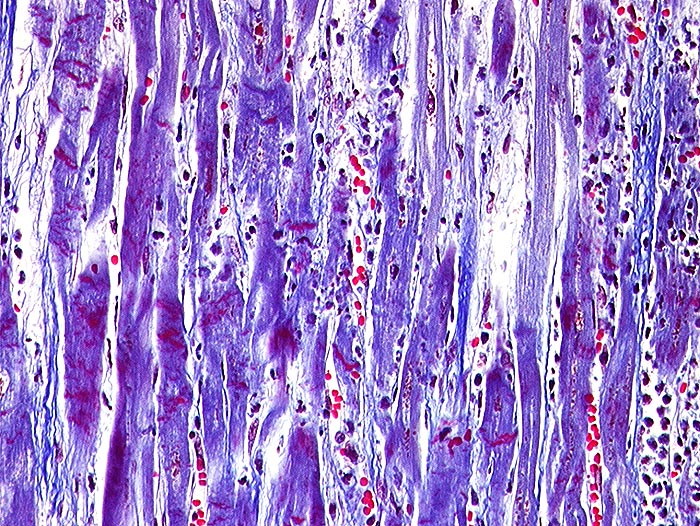

AP/ Akuter Myokardinfarkt

Akuter Myokardinfarkt

vaskulär / Durchblutungsstörung

Kardiovaskuläres System

Herz links